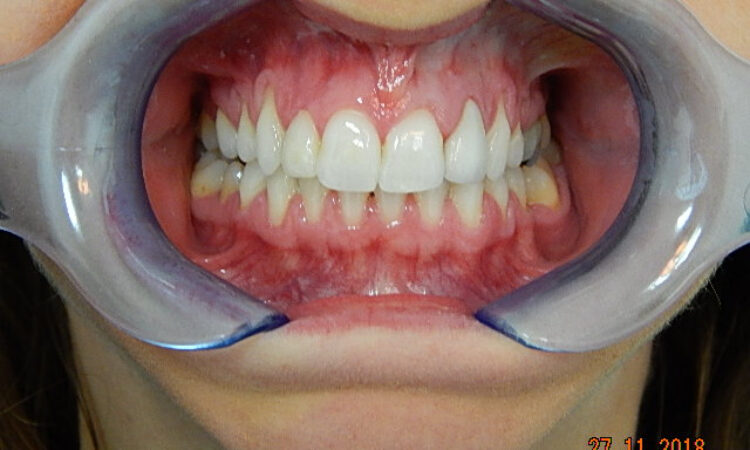

Before - puredental After - puredental

Case 18 - Invisalign®